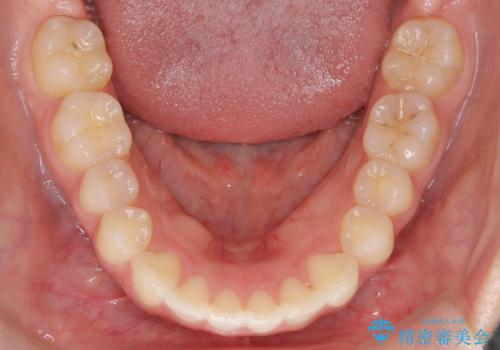

- 前歯が出ていることを主訴に来院されました。

奥歯を後ろに動かしながらスペースを作ることで、前歯を下げることができ患者さんにも満足していただきました。